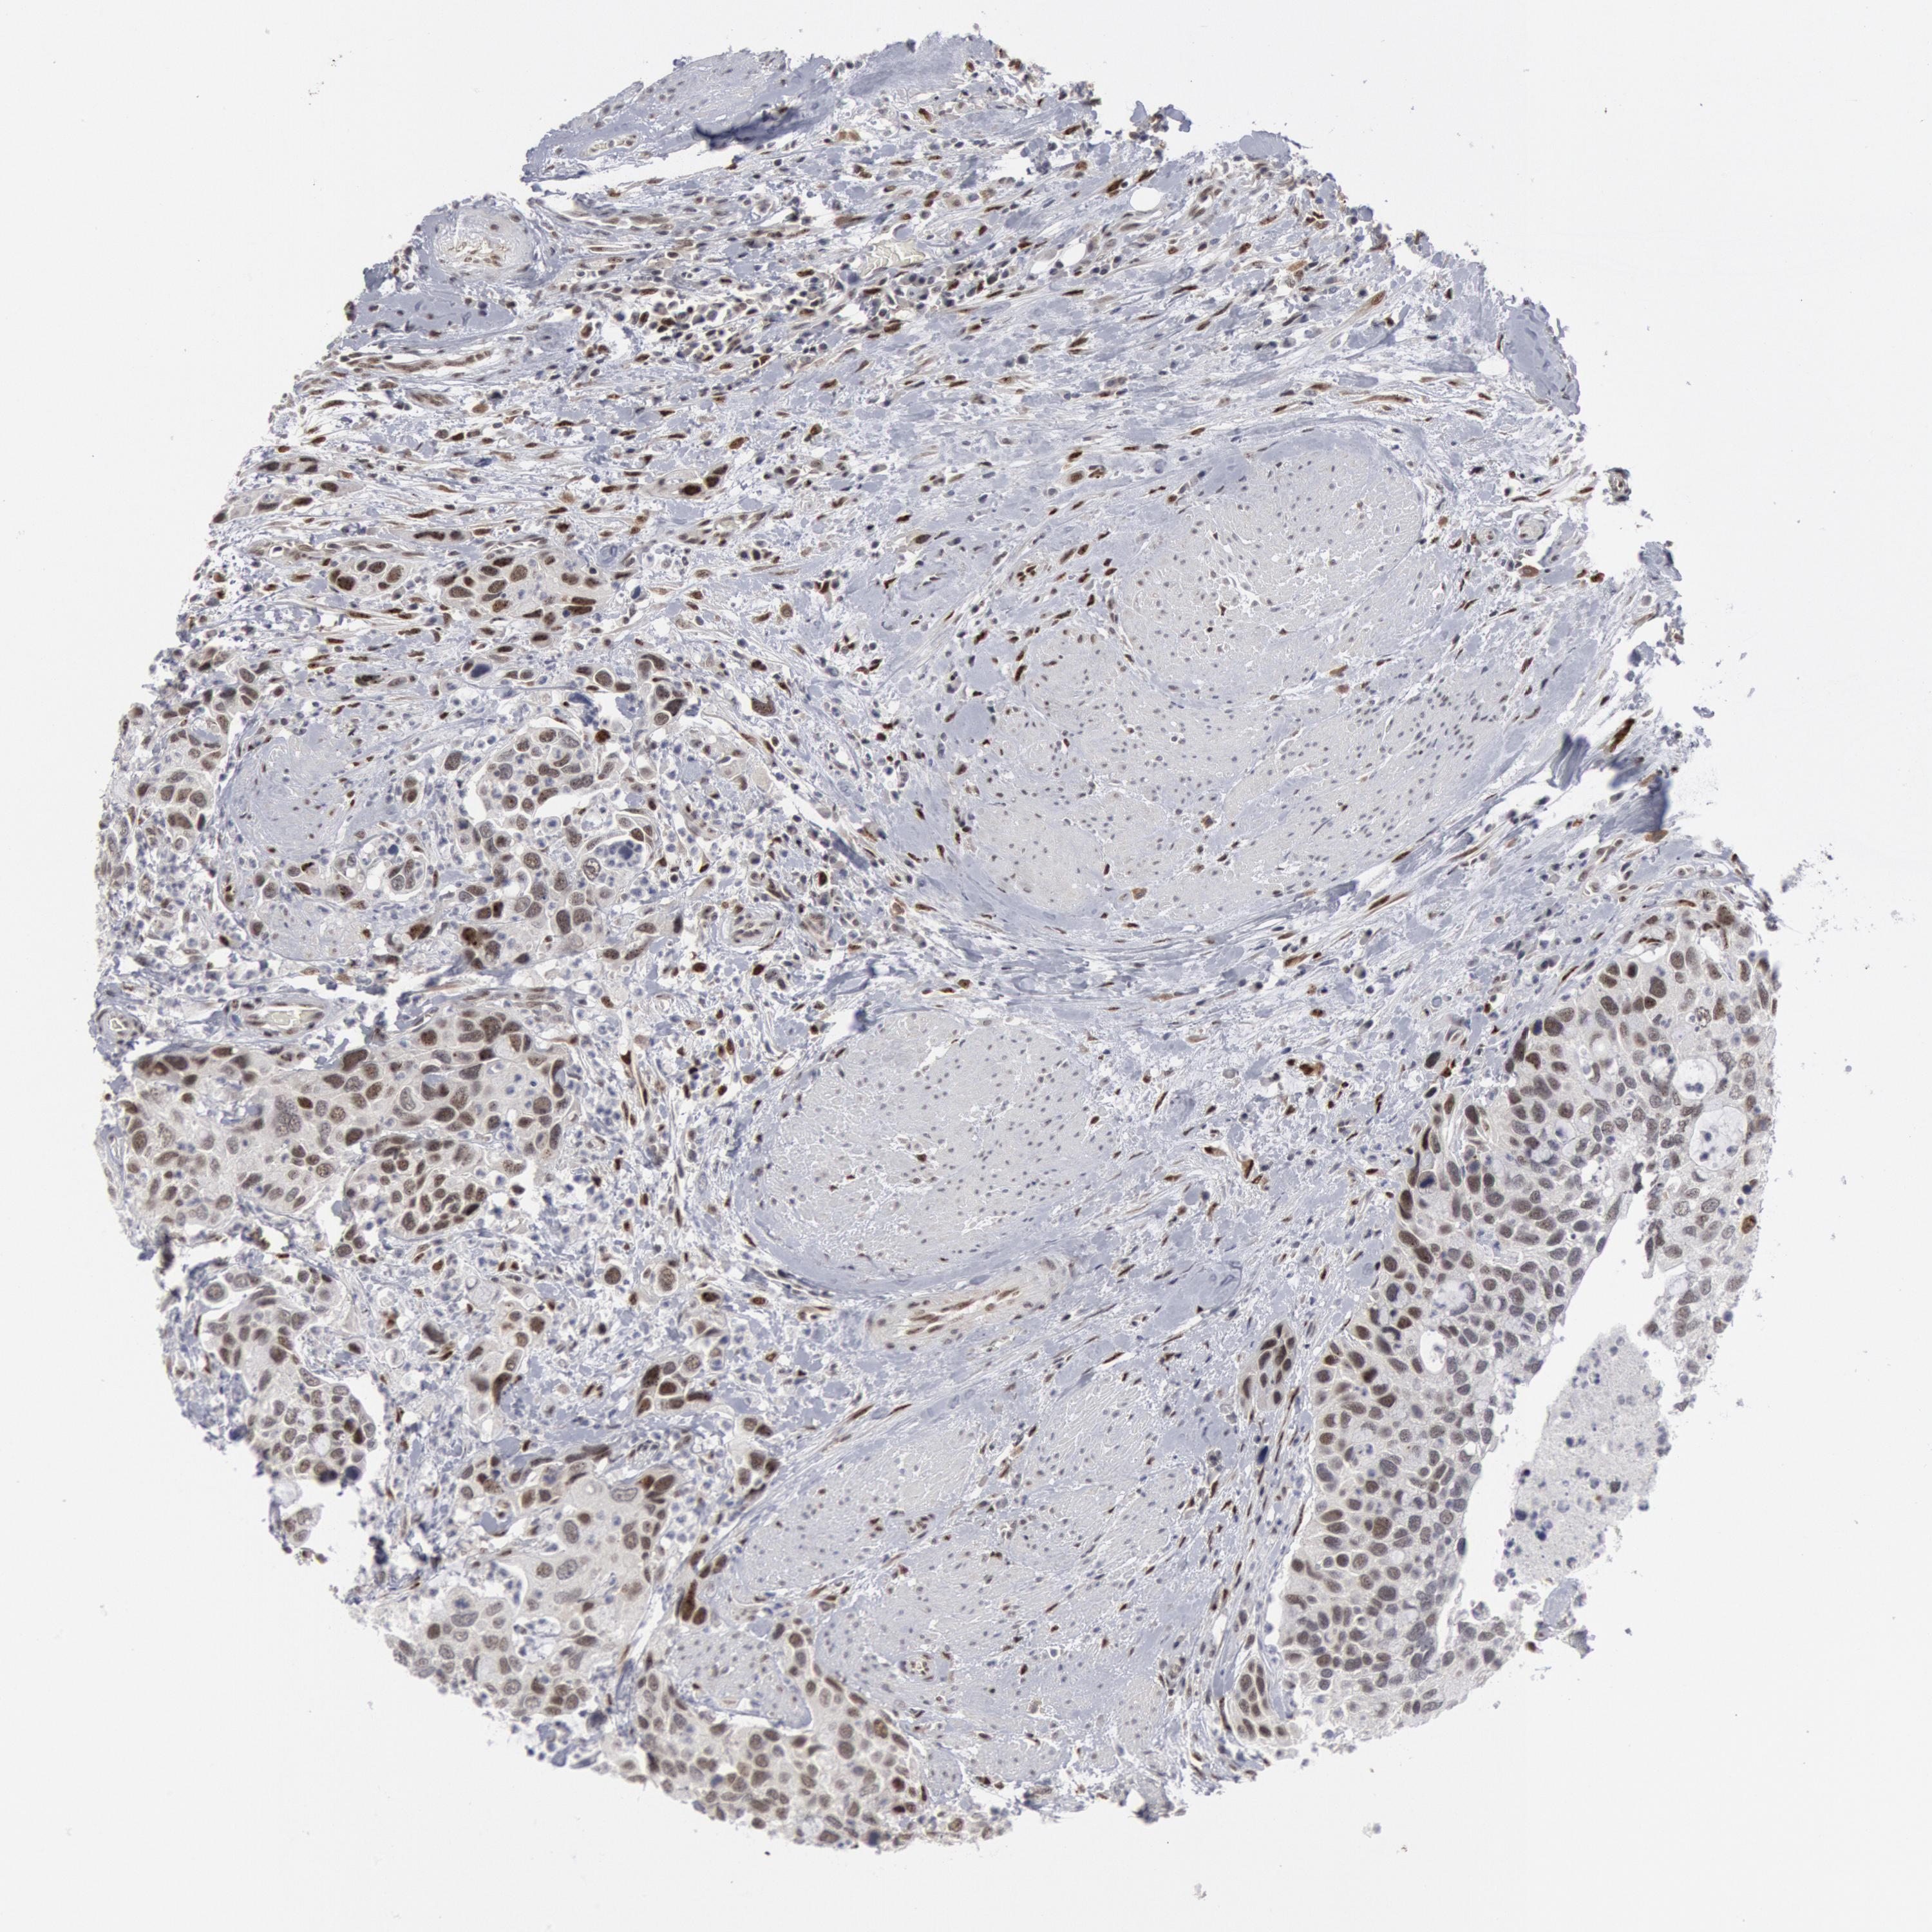

UROTHELIAL CANCER - Protein expressioni

A mouse-over function shows sample information and annotation data. Click on an image to view it in a full screen mode. Samples can be filtered based on level of antibody staining by selecting one or several of the following categories: high, medium, low and not detected. The assay and annotation is described here.

Antibody stainingi

Antibody staining in the annotated cell types in the current human tissue is reported as not detected, low, medium, or high, based on conventional immunohistochemistry profiling in selected tissues. This score is based on the combination of the staining intensity and fraction of stained cells.

Each image is clickable and will lead to virtual microscopy that enables deeper exploration of all samples and also displays staining intensity scores, fraction scores and subcellular localization as well as patient and tissue information for each sample.

HPA001252

CAB022326

CAB080477

CAB080478

CAB080479

Staining

High

Medium

Low

Not detected

Intensity

Strong

Moderate

Weak

Negative

Quantity

>75%

75%-25%

<25%

None

Location

Nuclear

Cytoplasmic/membranous

Cytoplasmic/membranous,nuclear

Urothelial carcinoma, High grade

Urothelial carcinoma, Low grade

Adenocarcinoma, NOS